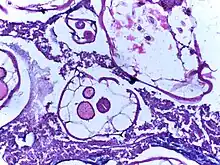

_(15806559973).jpg.webp)

.jpg.webp)

If complications of helminthiasis, such as intestinal obstruction occur, emergency surgery may be required.[9][56] Patients who require non-emergency surgery, for instance for removal of worms from the biliary tree, can be pre-treated with the anthelmintic drug albendazole.[9]